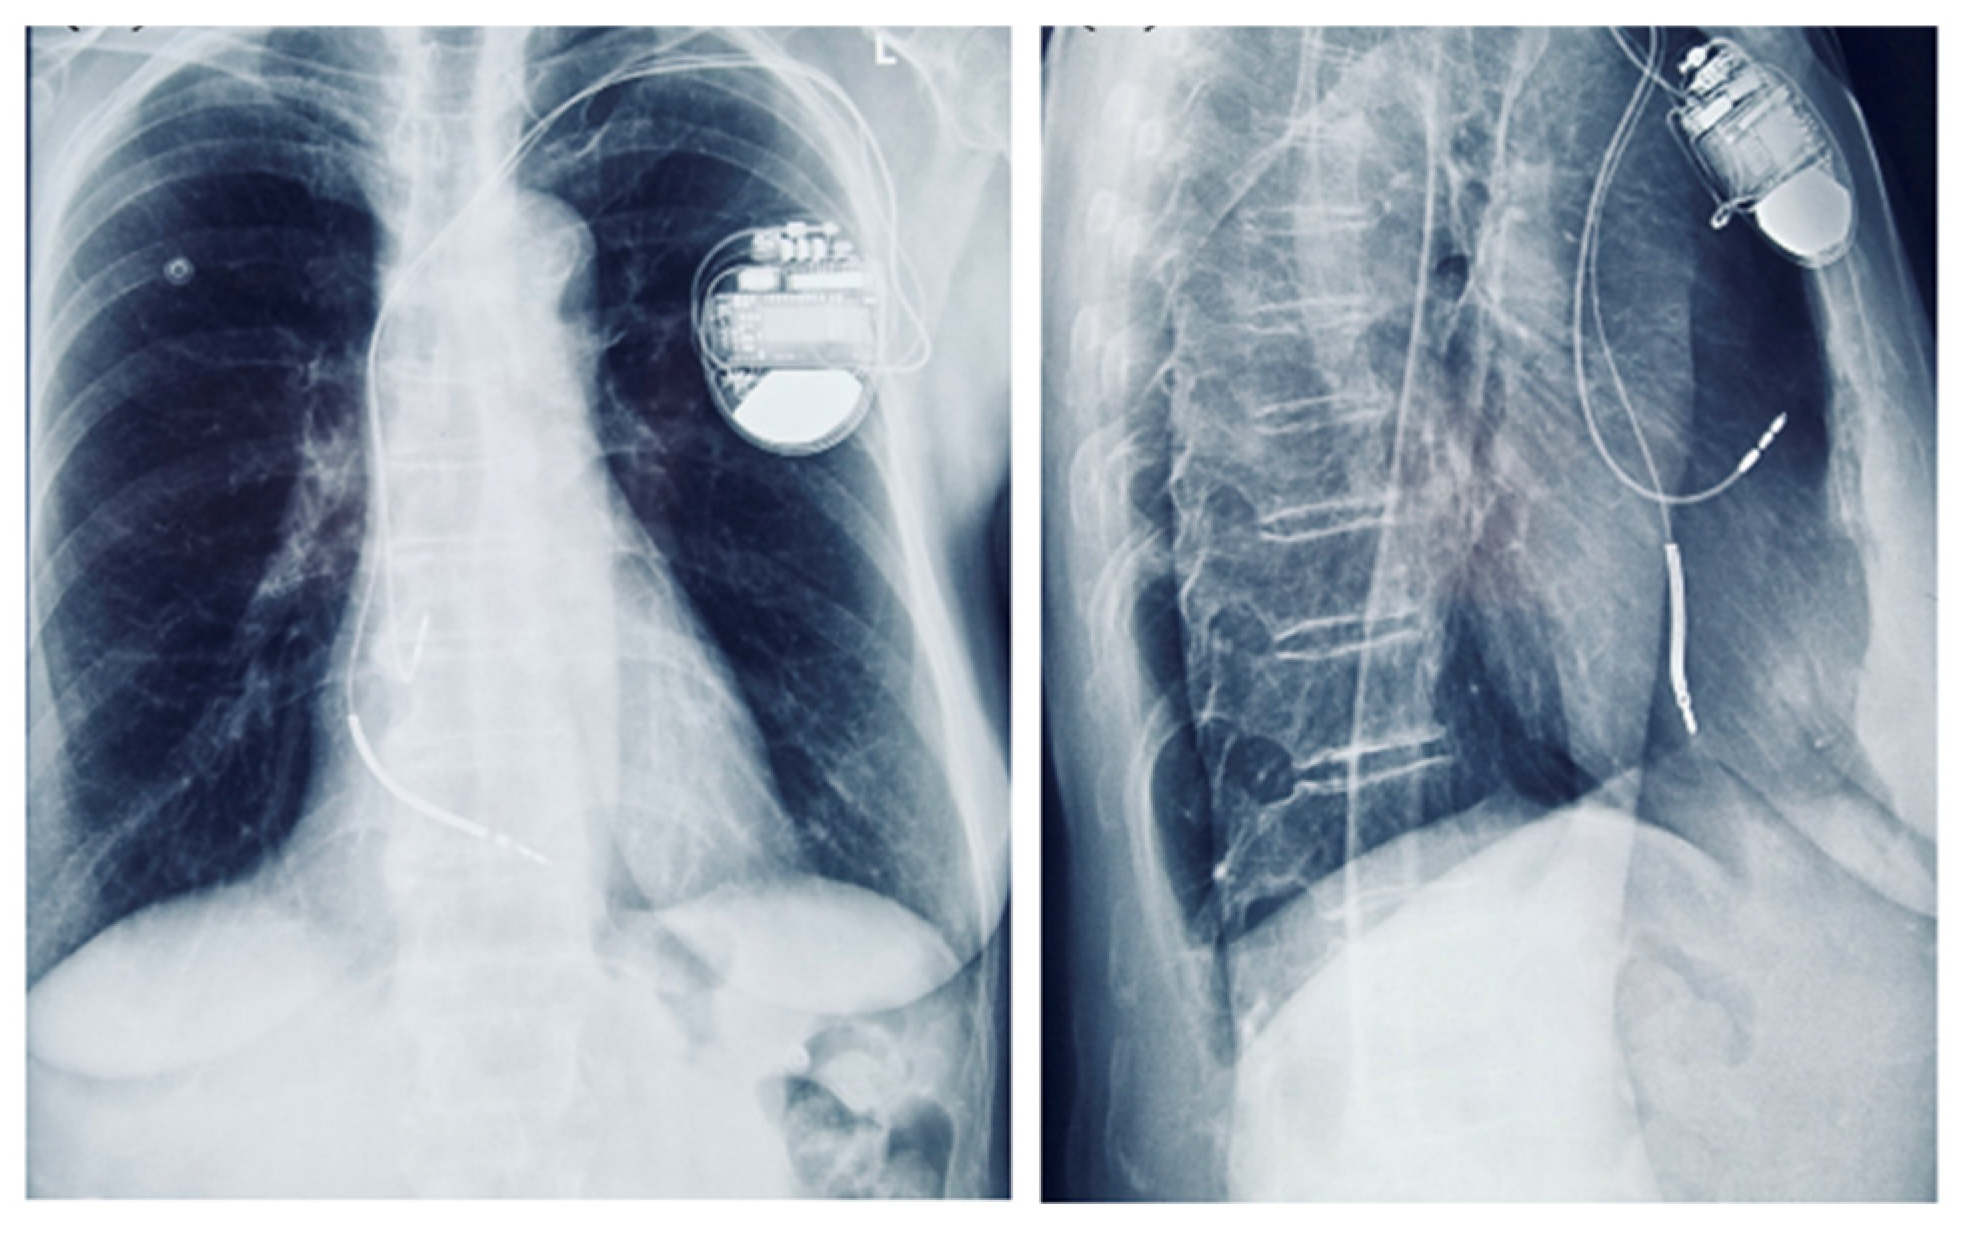

Although the patient had no sustained VT and no LGE on CMR, implantable cardioverter-defibrillator (ICD) implantation was justified by the presence of multiple high-risk features. Following Heart Team discussion, an ICD was implanted for primary prevention of sudden cardiac death, in the context of arrhythmogenic mitral valve prolapse (AMVP) with high-risk features (Figure 9). Moreover, given the additional need for beta-blocker therapy and the patient’s baseline bradycardia, a dual-chamber ICD was selected to provide both arrhythmic protection and pacing support. The presence of bradycardia, together with the requirement for antiarrhythmic medication, represented an additional factor influencing the decision for ICD implantation.

Chest radiograph showing a dual-chamber implantable cardioverter-defibrillator (ICD) in anteroposterior and lateral views.

Although our patient did not exhibit sustained ventricular tachycardia, late gadolinium enhancement on cardiac MRI, or undergo electrophysiological testing, the decision to implant an ICD was based on the convergence of multiple high-risk features (Figure 12), in line with the 2022 EHRA Expert Consensus [4]. An electrophysiological study (EP study) was not performed, as the patient declined the procedure. Importantly, the 2022 EHRA consensus does not mandate EP testing in the risk stratification of AMVP, and ICD implantation may be considered in the presence of multiple high-risk features, even in its absence. After a multidisciplinary Heart Team evaluation, the patient was considered at elevated risk for sudden cardiac death (Figure 12). Furthermore, initiation of antiarrhythmic therapy with a beta-blocker was considered necessary to reduce the arrhythmia burden; however, given the patient’s baseline bradycardia (~55 bpm), pacing support was anticipated. This clinical context favored the implantation of a dual-chamber ICD rather than a single-chamber system. Taken together, the integration of phenotypic, arrhythmic, and clinical risk markers supported the decision for device therapy, despite the absence of sustained VT or LGE, as a proactive measure for primary prevention in a patient at high risk for sudden cardiac death. Beta-blocker therapy with bisoprolol was initiated to reduce arrhythmia burden.